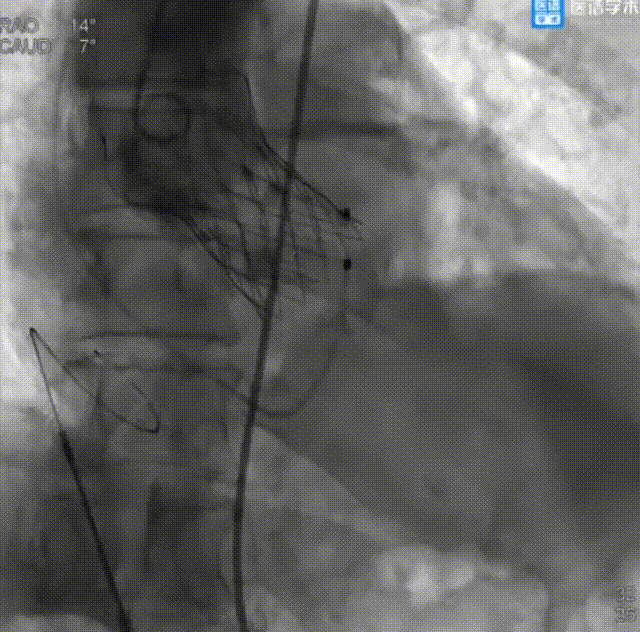

冠状动脉造影+PCI介入治疗:

造影提示左主干严重钙化病变

支架成功释放

支架释放后冠脉造影

患者全麻成功后,先经右股动脉置入6 F动脉鞘管并送入JL 4.0、JR 4.0造影导管行冠状动脉造影。结果显示左主干全程弥漫钙化病变,开口钙化狭窄80%;左前降支近中段全程弥漫钙化病变,最重狭窄70%,D1开口狭窄60%;左回旋支开口狭窄80%,近段弥漫钙化病变,最重狭窄70%;右冠状动脉中段原支架开放良好,支架入口前狭窄30%,远段狭窄70%。

经讨论,决定对LM行PCI治疗,先送入切割球囊至LM开口病变处行预扩张,后送入支架释放,即刻造影结果显示无残余狭窄及夹层,且前向血流TIMI Ⅲ级。